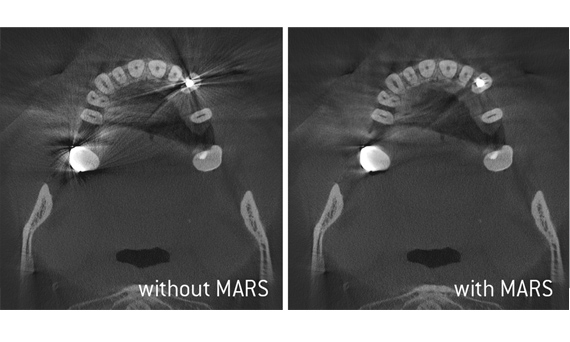

With all of our Dentsply Sirona 3D imaging units, Axeos and Orthophos S 3D, you get state-of-the-art imaging processes designed for optimal clinical diagnostic support. When capturing a 3D X-ray with one of our devices, several hundred indivdual images are taken and then this data is combined within the matter of seconds to create a final 3D image of the jaw area for your diagnosis. The practitioner is then able to take a “virutal tour” of the scan and assess the data from every dimension.